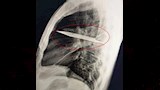

وأظهرت الفحوص السريرية أن الجزء الأيمن من صدره لا يتمدد بالكامل أثناء التنفس، فيما كشفت الأشعة السينية وجود شفرة سكين كبيرة عالقة في تجويف الصدر، ممتدة من الظهر إلى مقدمة القفص الصدري، ومحاطة بطبقات من القيح والأنسجة الميتة.

وتبين أن الرجل تعرض قبل ثماني سنوات لطعنات متكررة في الصدر والظهر والبطن والوجه خلال مشاجرة عنيفة، واكتفى وقتها بتلقي إسعافات أولية للجروح السطحية دون إجراء فحوص تصويرية.